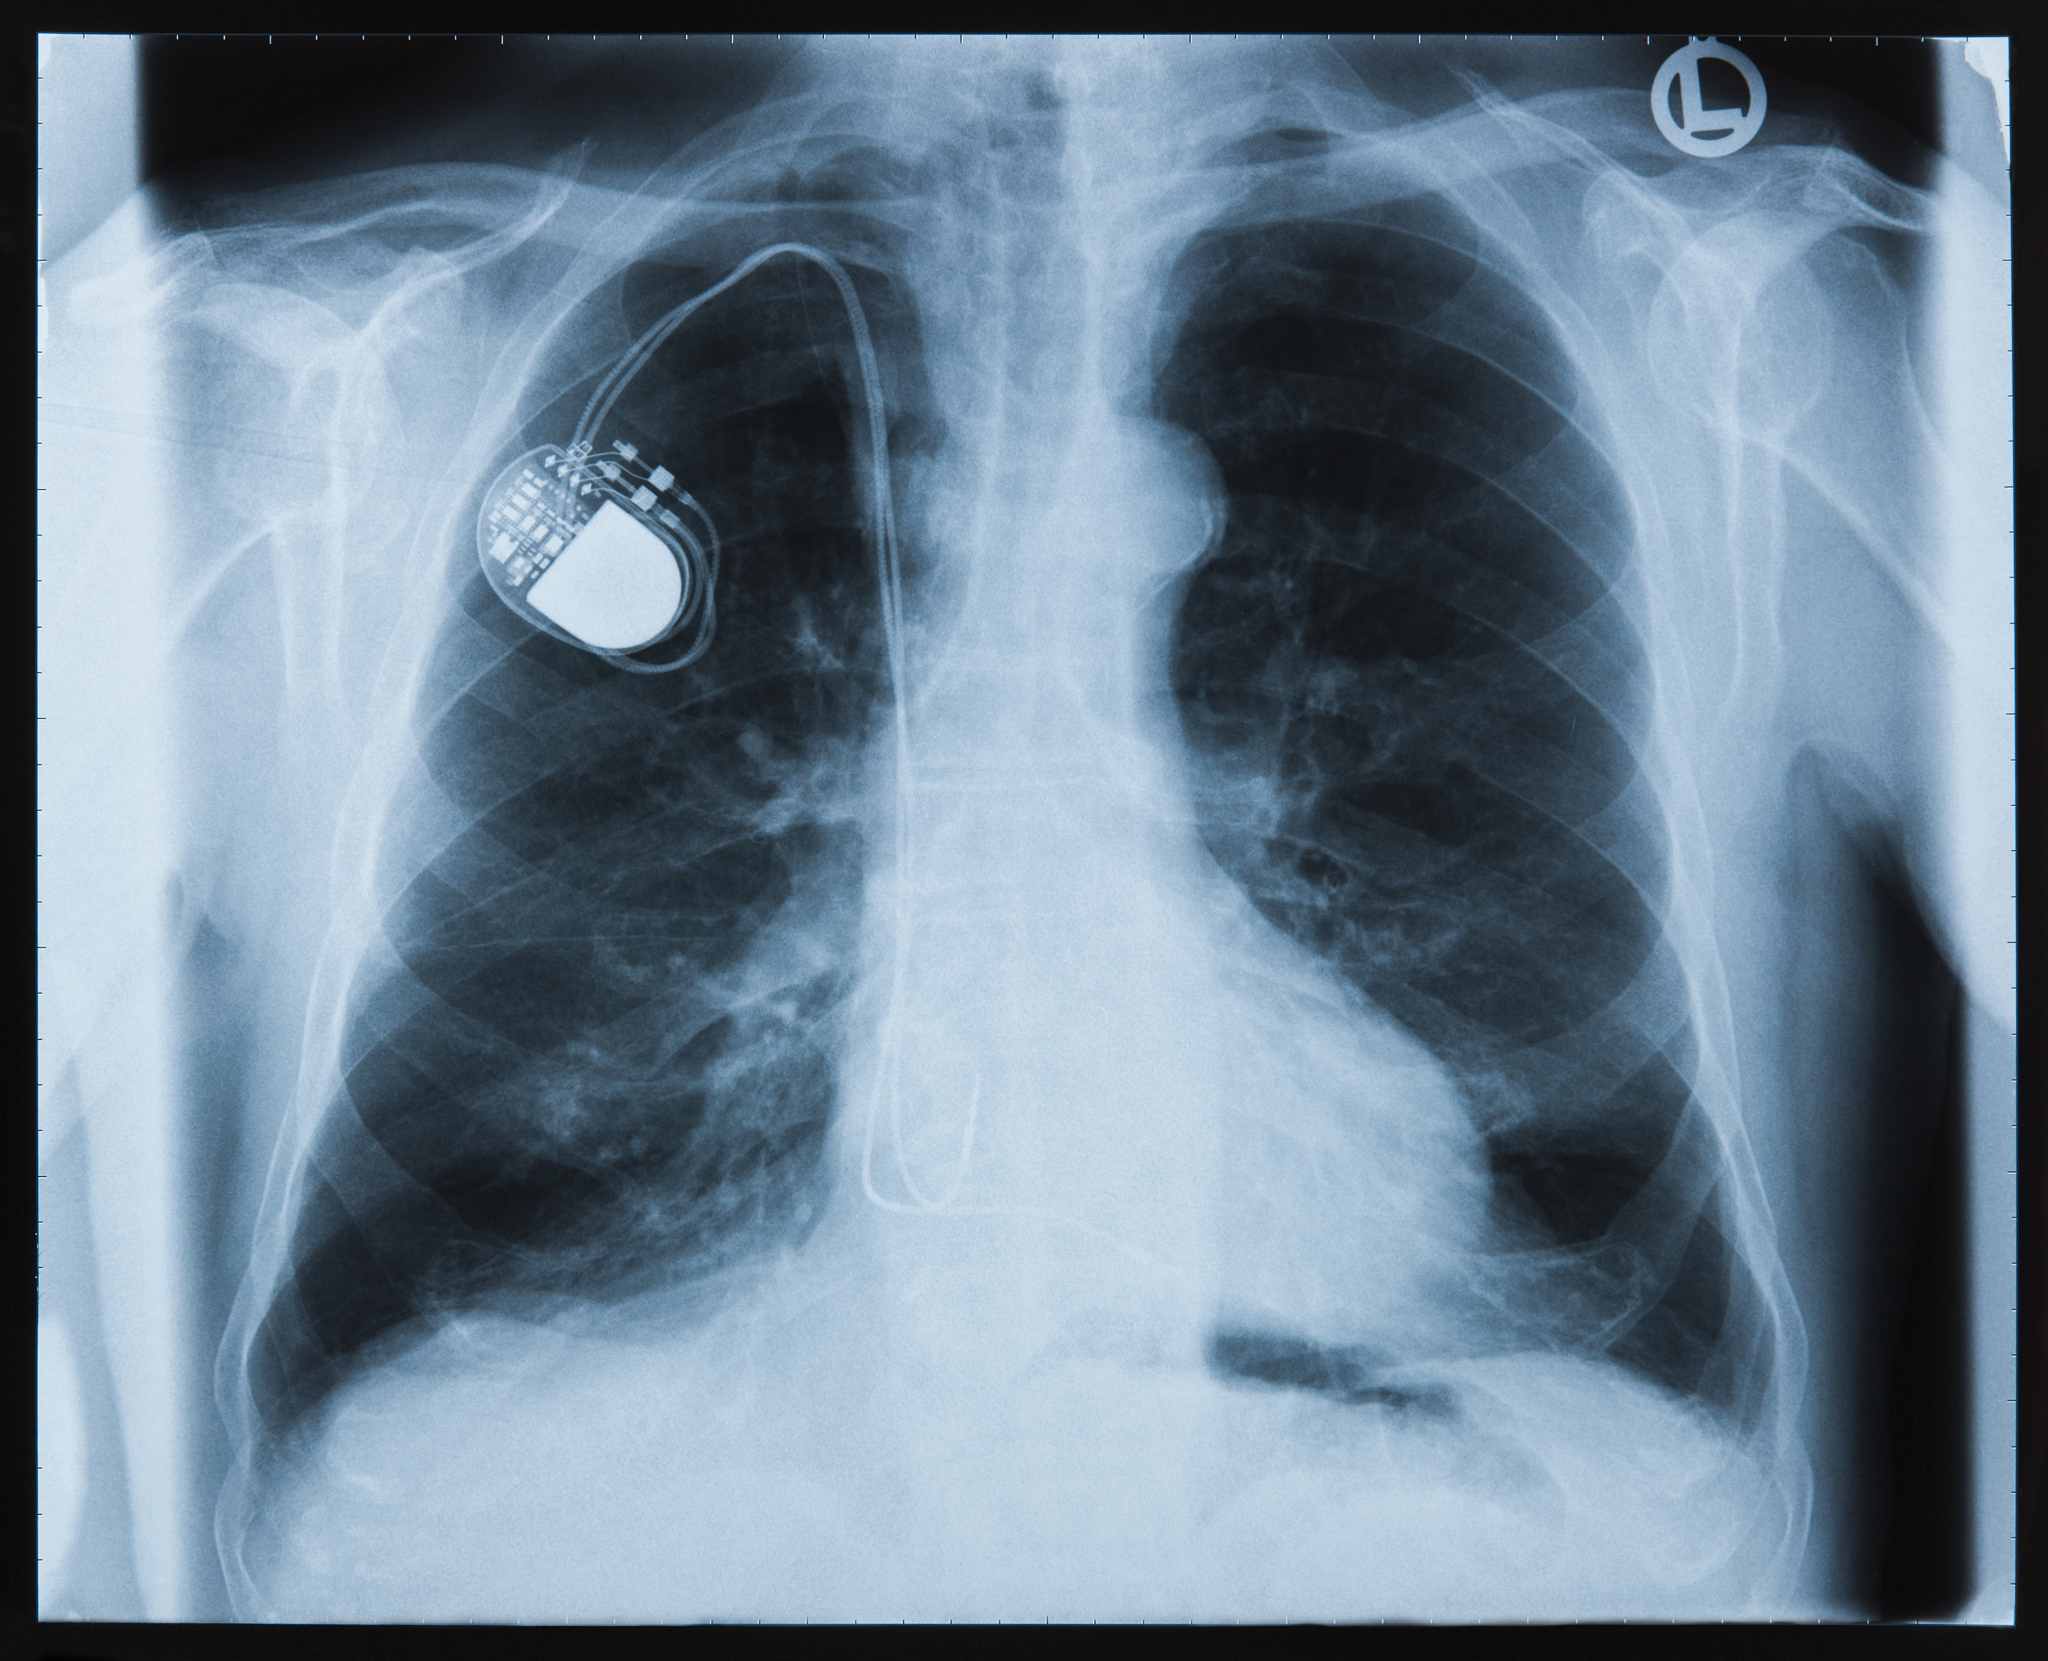

4. 胸部X线检查:评估肺部情况和心脏位置。